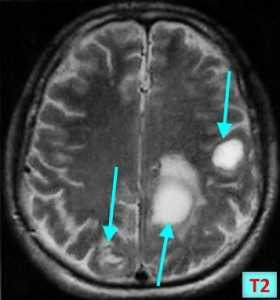

Позитронно-эмиссионная томография (ПЭТ) в диагностике вторичных опухолей ЦНС

Типичная картина вторичных очагов в головной мозг при ПЭТ — наличие зон повышенного захвата радиофармпрепарата (ФДГ — фтордезоксиглюкоза, либо препаратов меченых аминокислот, таких как метионин) с наличием очагов некроза, протяженных зон отека со сниженным захватом ФДГ.

Как выглядят метастазы на ПЭТ-КТ? Здесь виден опухолевый очаг в правой затылочной доле, значительно накапливающий РФП (меченный радиоактивным фтором метионин). ПЭТ-КТ — метод, признанный «золотым стандартом» не только в выявлении метастазов в мозг, но и позволяющий достоверно отличить их от других образований (кисты, абсцессы, гематомы, каверномы и т.п.). От тщательного анализа ПЭТ зависит результат диагностики.